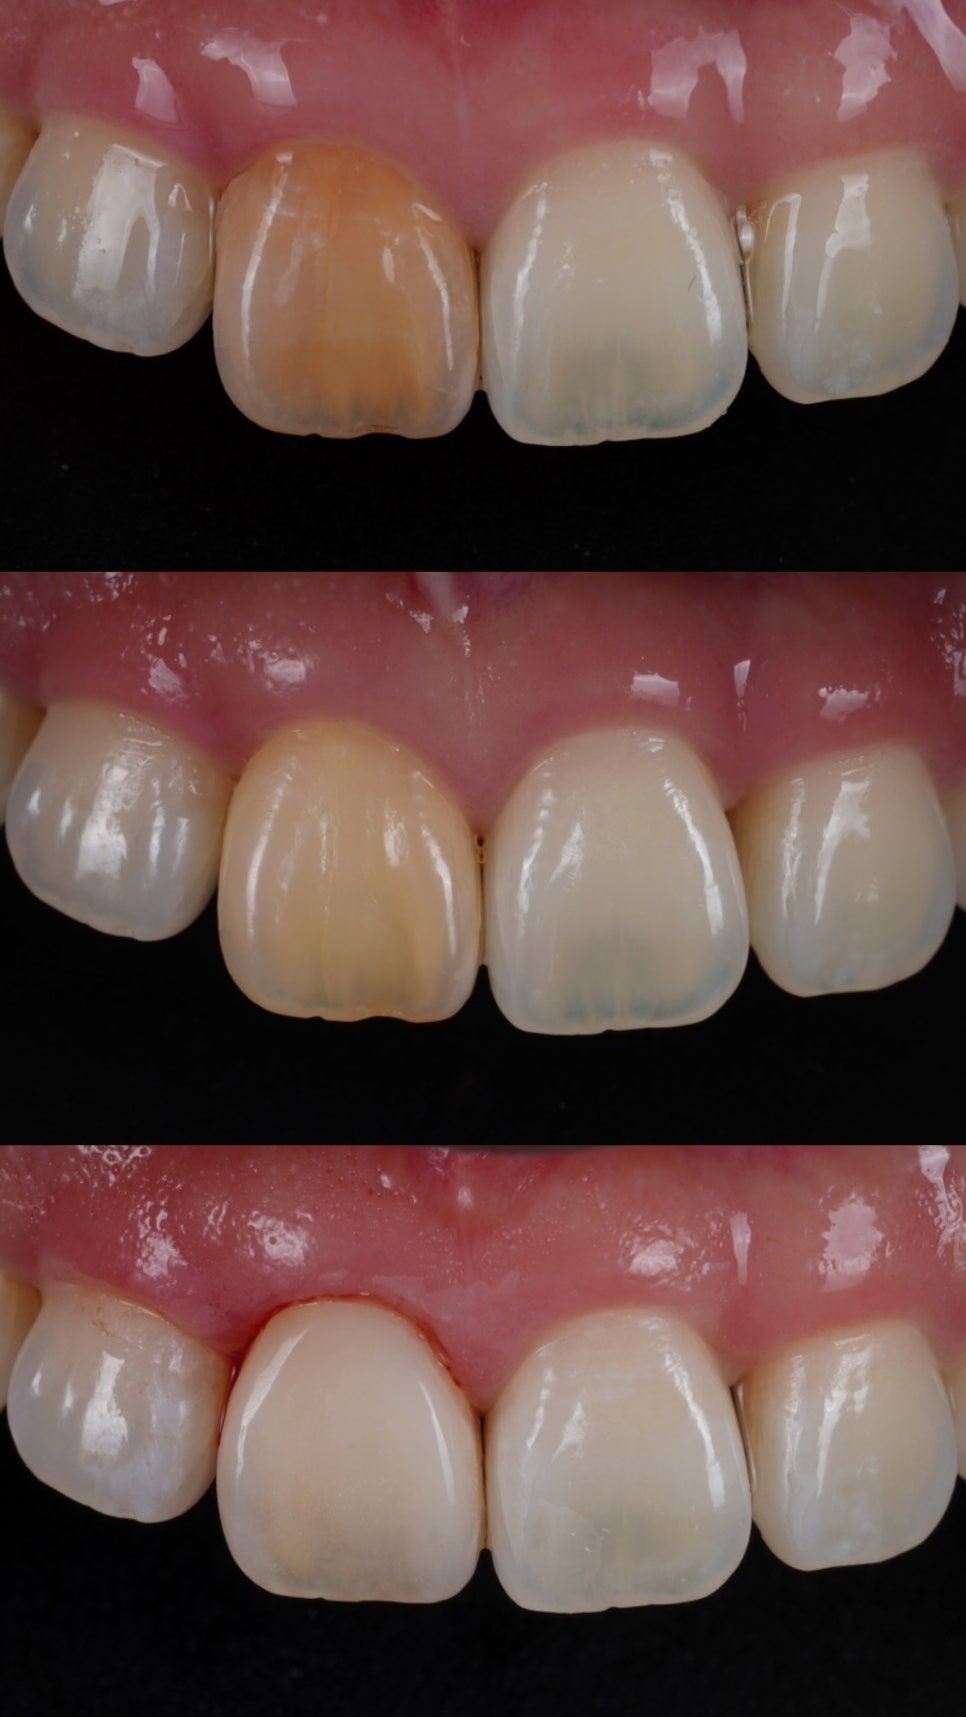

오래전, 외상으로 인해

신경이 죽으면서 앞니가 심하게

변색되었는데요.

실활치 미백을 진행했어요.

촬영일 : 250905

아주 오래 전에 타치과에서

신경치료를 실패한

경험이 있으셨습니다.

오래된 약재를 제거하고

깨끗하게 비운 신경관을 밀폐한 후

치아 내부에 미백 약제를 넣었어요.

변색 원인이 된 내부 성분을 분해하고

점차 밝은색으로 회복되도록 유도했어요.

마치 치아 속에 꺼져 있던 조명을

하나 켜주는 과정이라고

보시면 이해하기 쉬워요.

촬영일 : 250905 / 250926 / 251001

촬영일 : 250905 / 251001